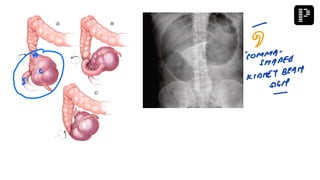

Q. A young female presenting with pain and vomiting in emergency. Clinical examination

reveals a swelling lateral and below pubic tubercle. X-ray shows intestinal obstruction. What

is most probable diagnosis?